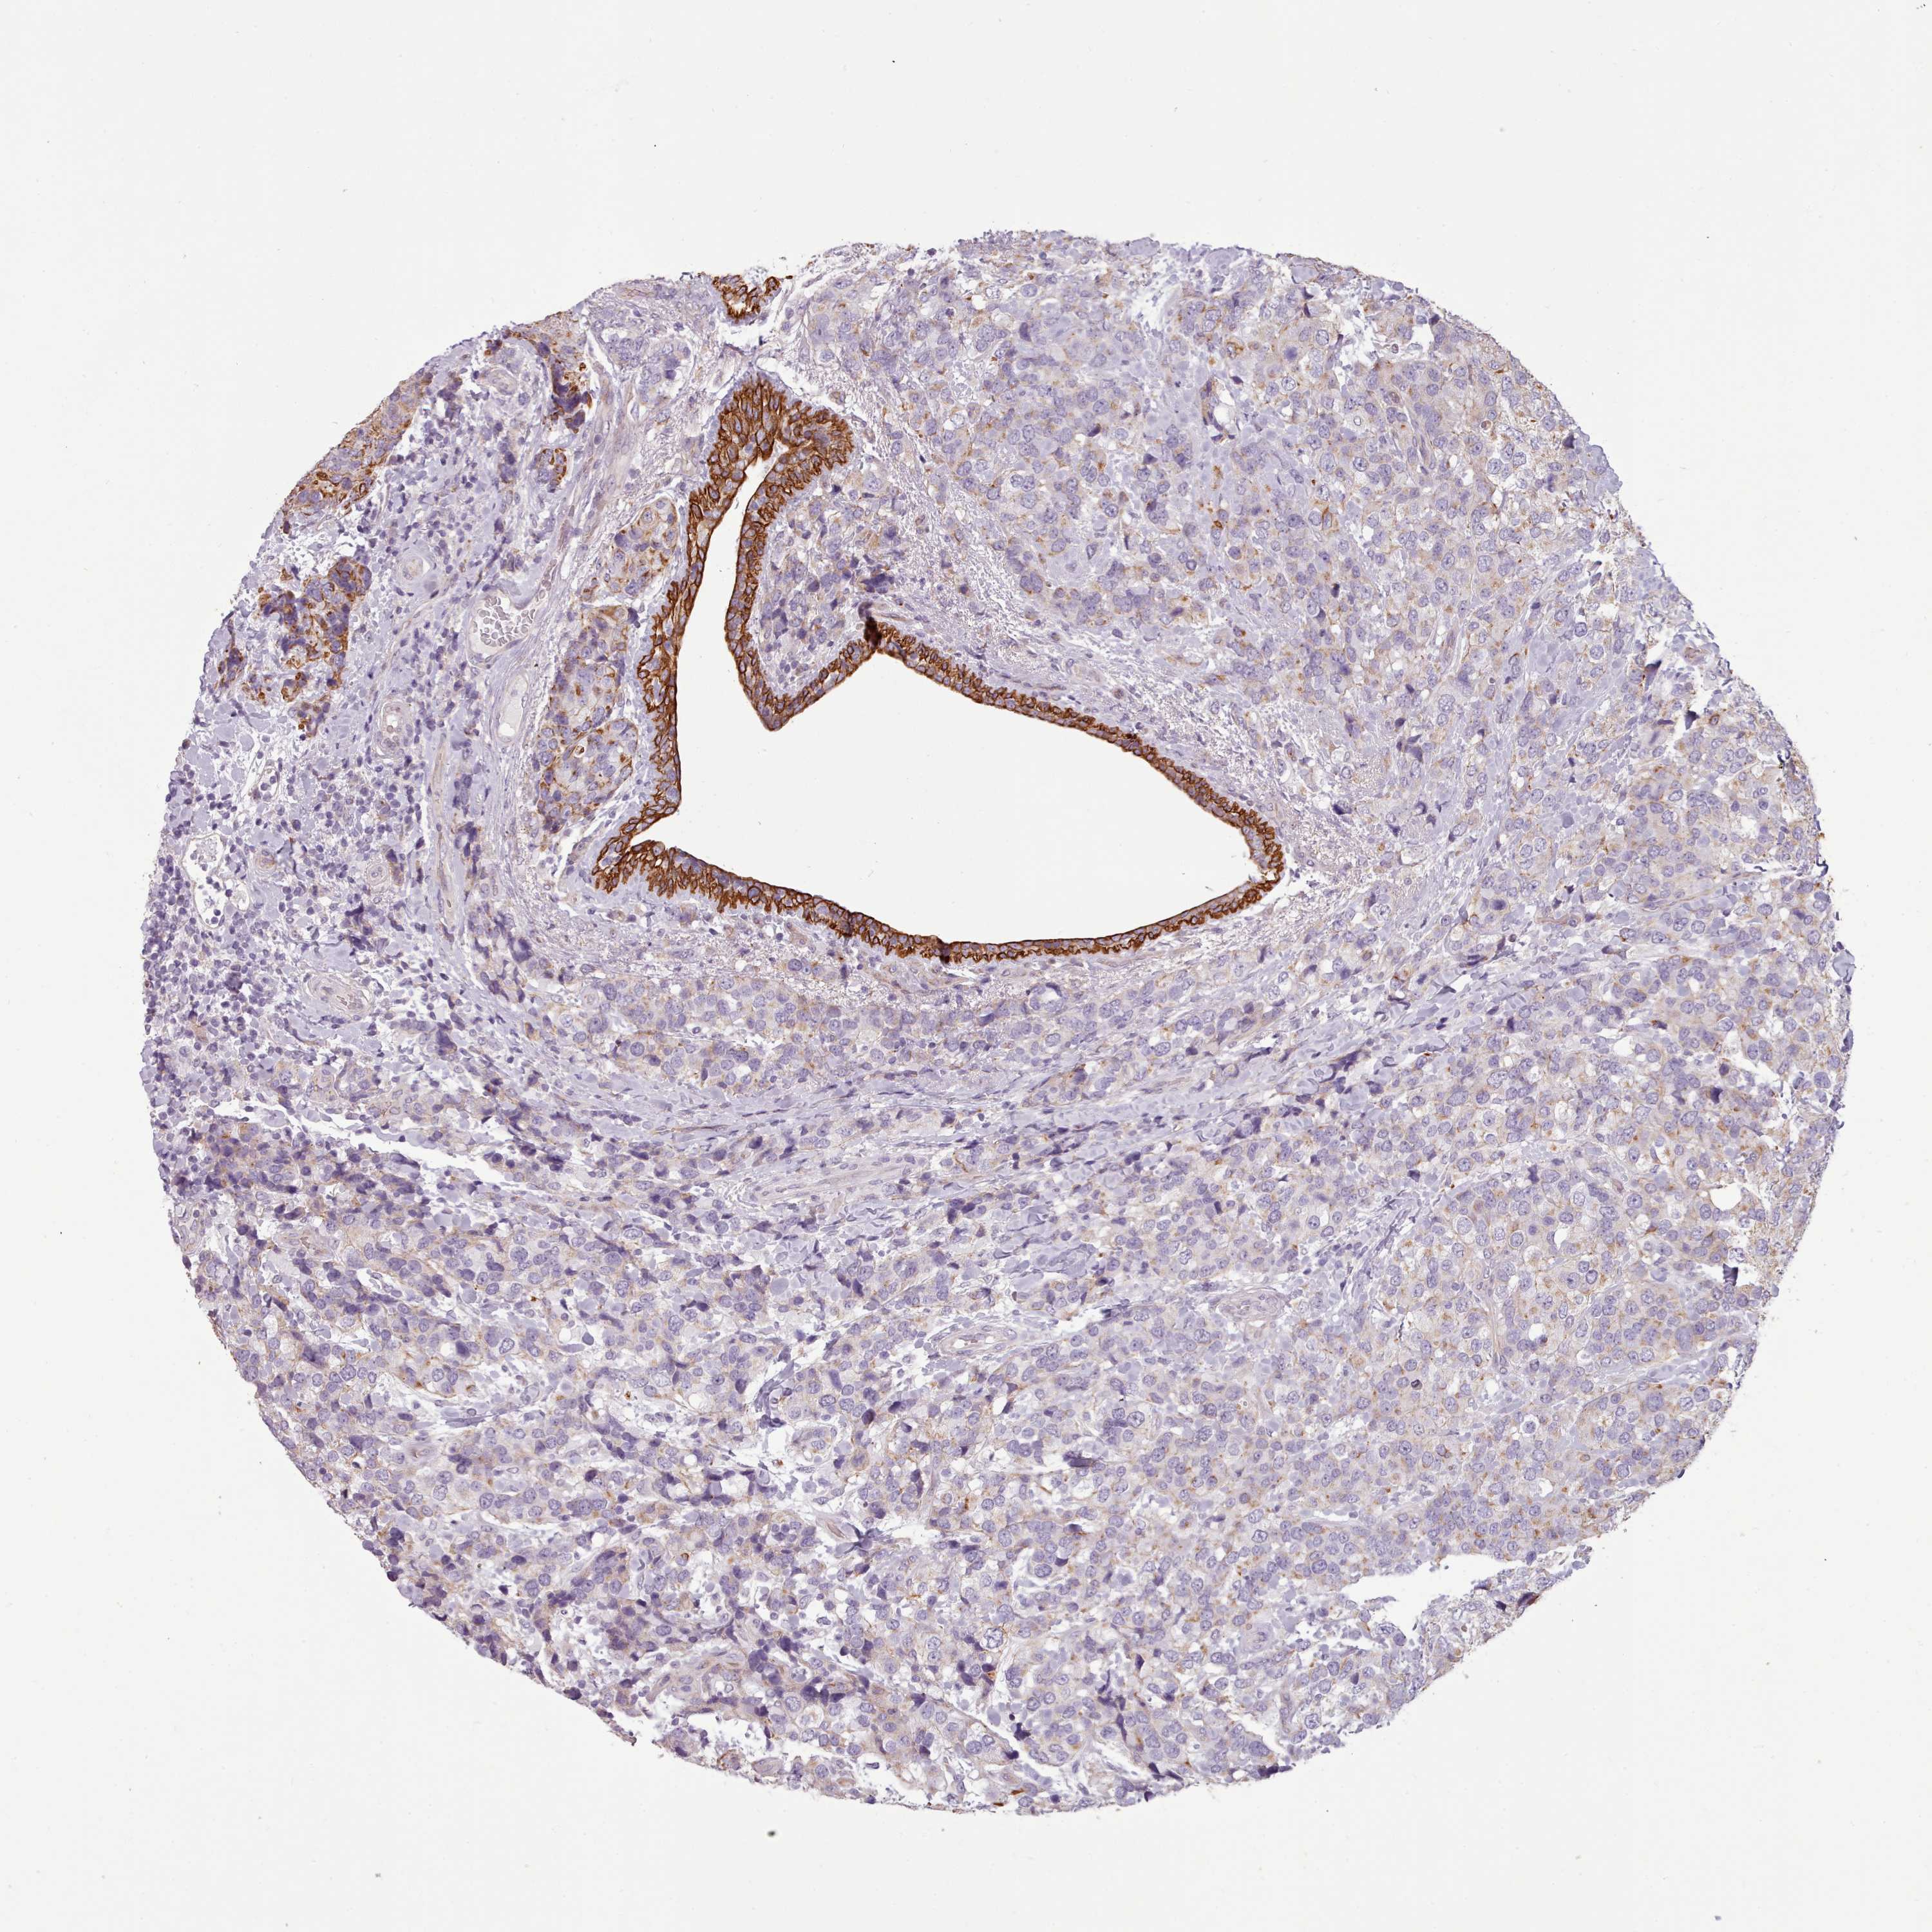

BRCA TCGA BRCA VALIDATION PROTEIN EXPRESSION

ANTIBODIES

AND

VALIDATION